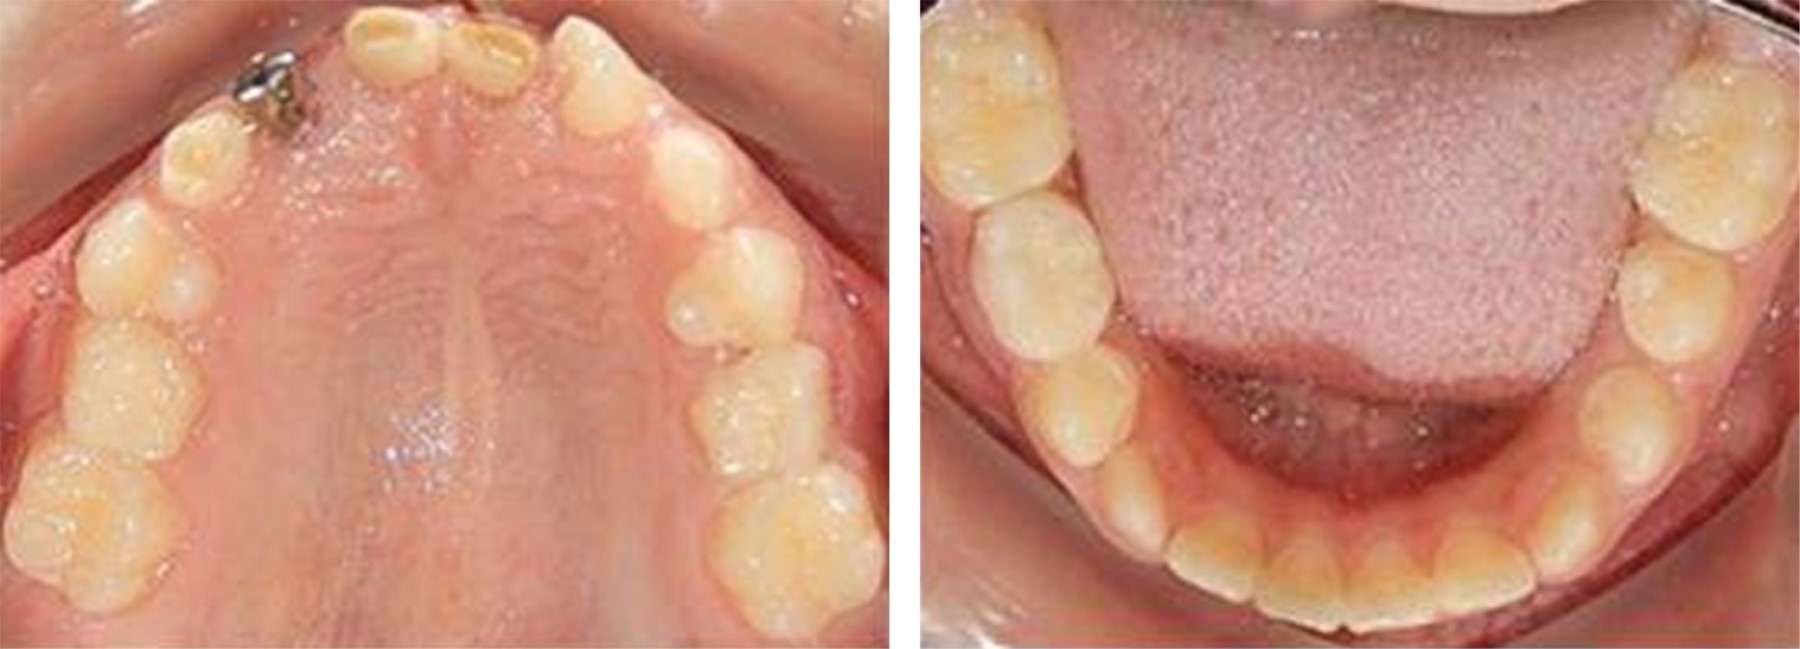

The upper and lower occlusal view (Figure 2). showed oval dental arches and upper moderate crowding with the presence of deciduous teeth